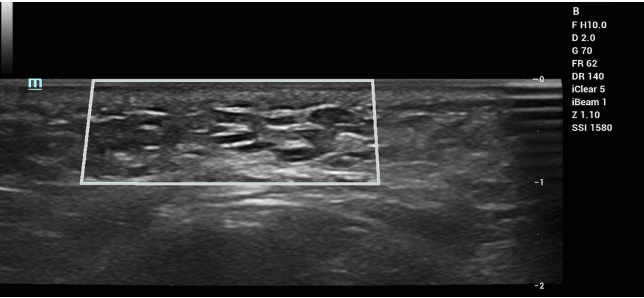

KARISMA (Collagen/HA Biostimulator): KARISMA® represents a recent advancement in collagen-based dermal fillers, formulated with recombinant human type I collagen polypeptide, high molecular weight HA, and carboxymethylcellulose (CMC). To date, ultrasound appearances specific to KARISMA have not been previously published. However, it can be hypothesized to display imaging characteristics similar to those of other collagen-based fillers—namely, a homogeneously hypoechoic implant that becomes isoechoic as exogenous collagen integrates into the surrounding tissue. The presence of CMC may initially generate reflective echoes, as CMC (a cellulose derivative) has been associated with hyperechoic signals and localized fibrosis (Figure 1).

Figure 1: Ultrasound imaging of KARISMA (3 days after injection). Imaging revealed multiple hypoechoic implants with a peripheral hyperechoic ring of carboxymethylcellulose.